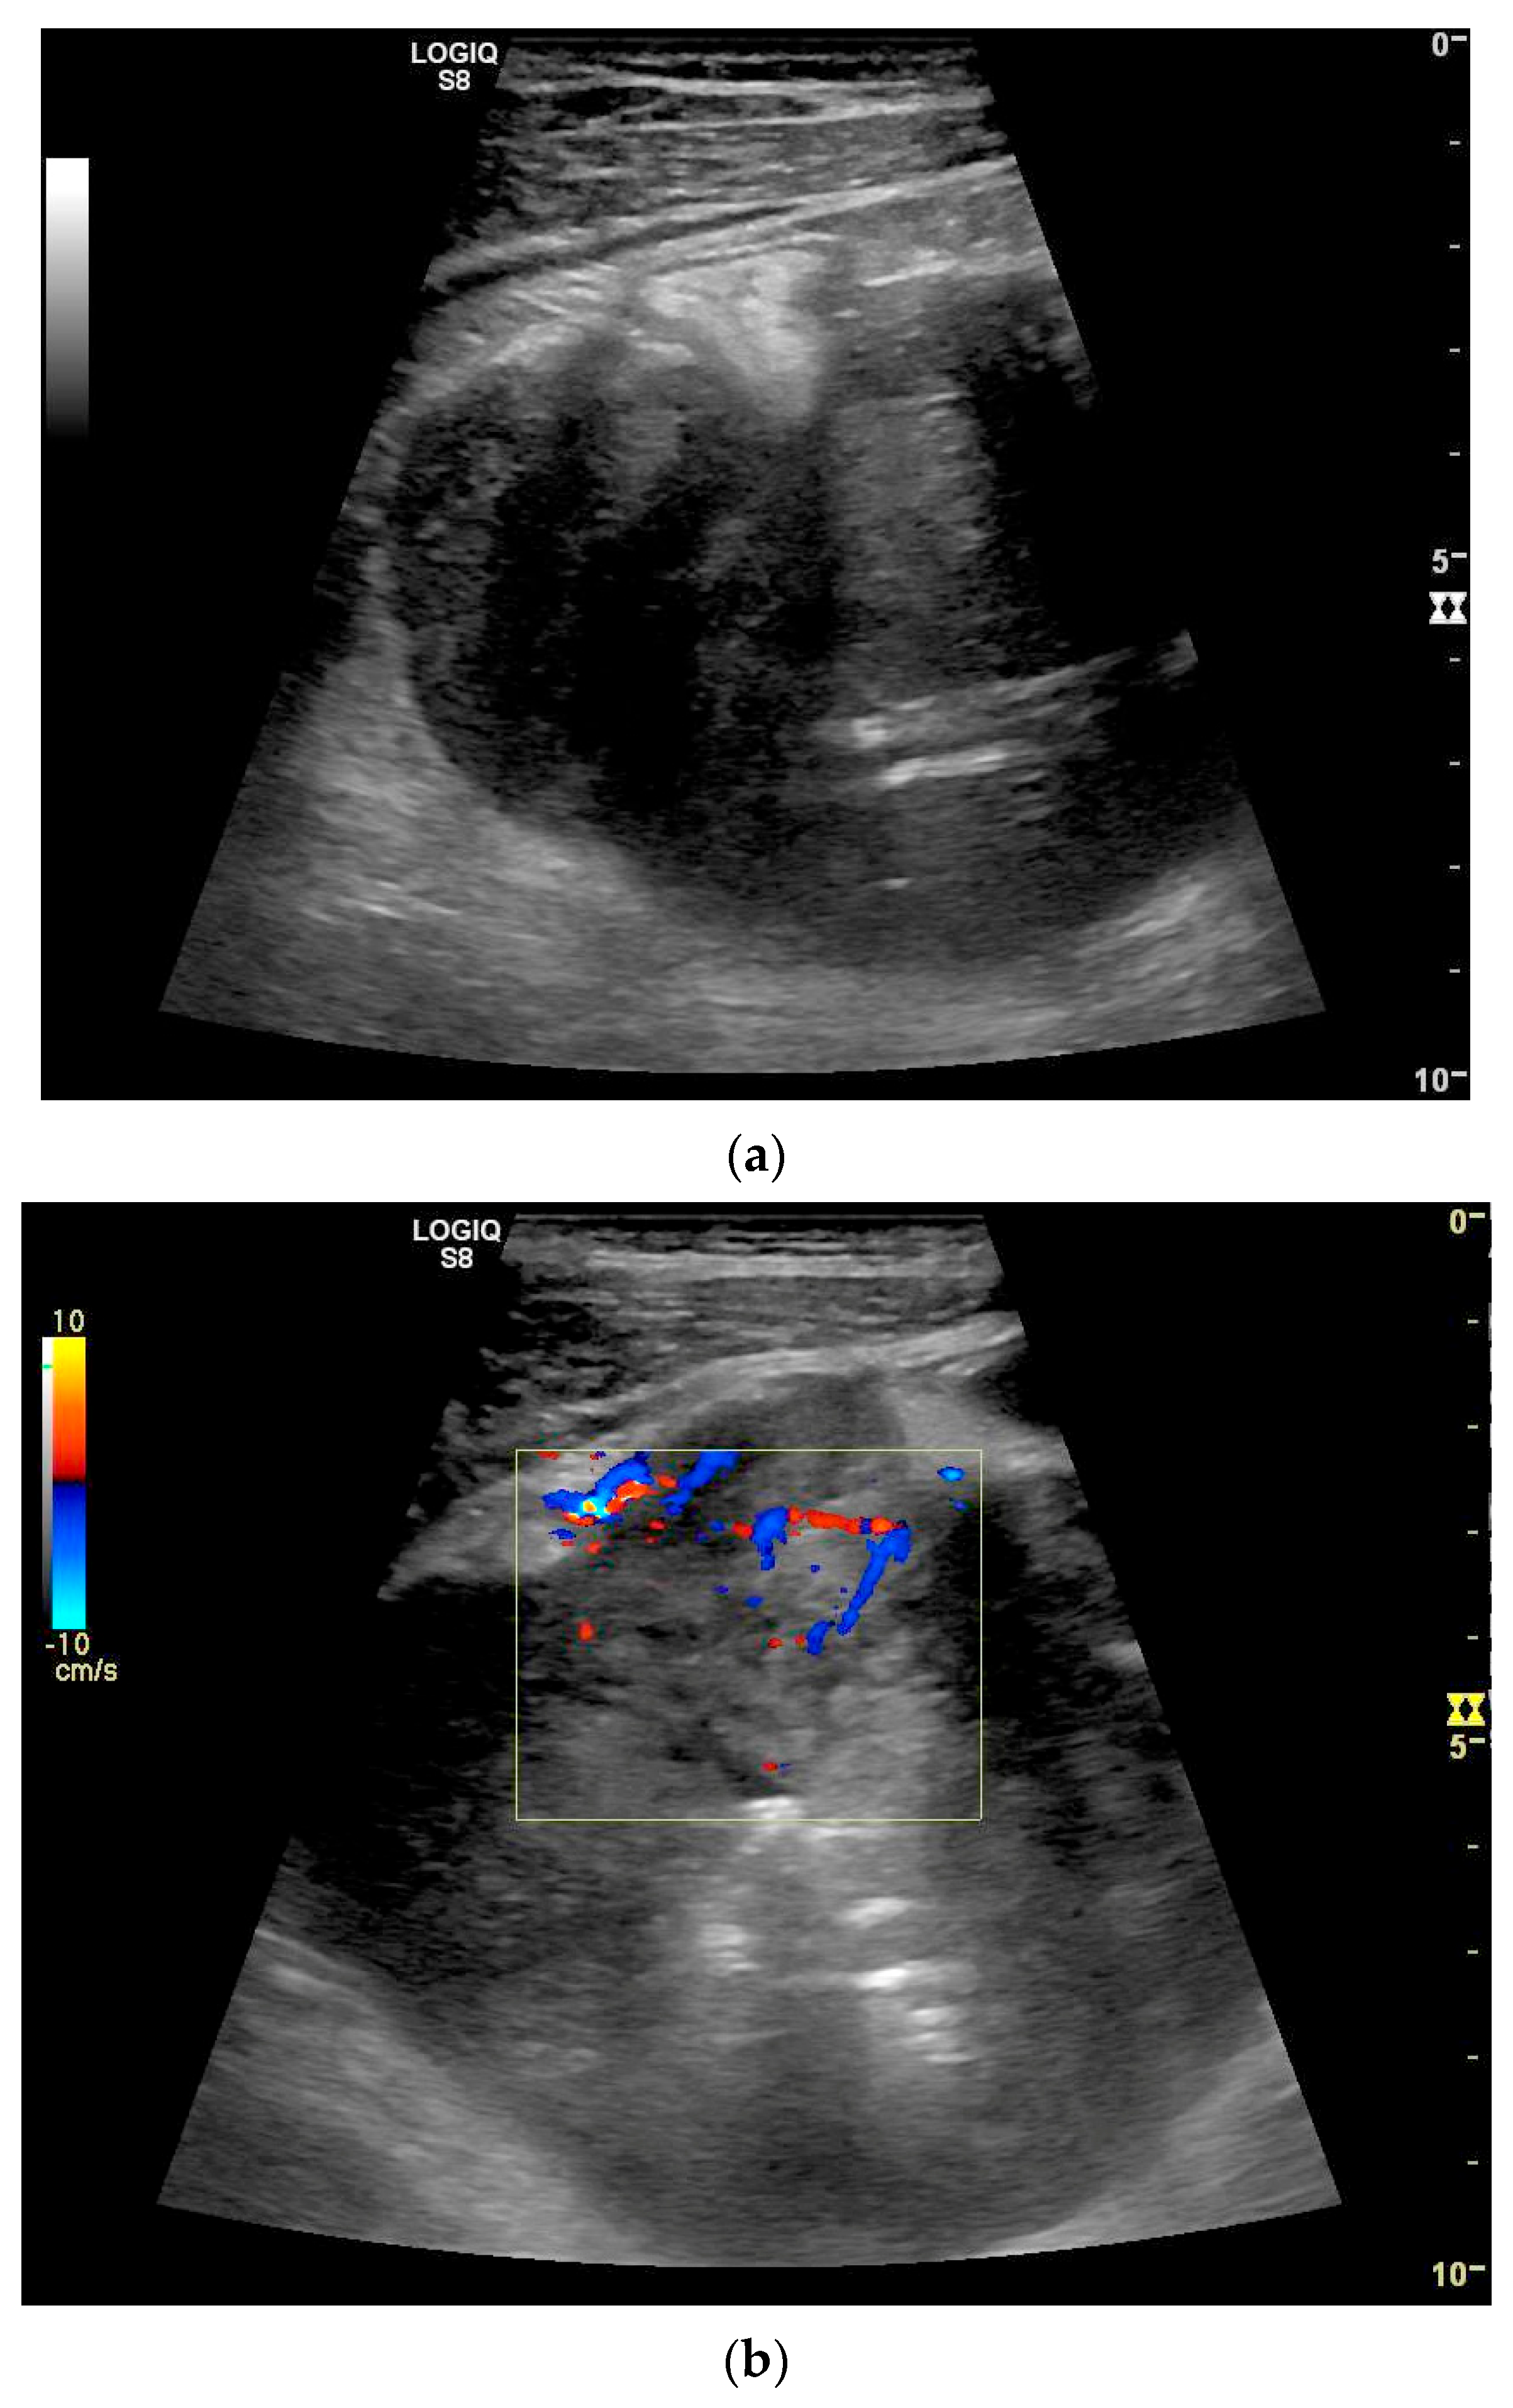

| Neuroendocrine tumor | Small, nodular hypoechoic wall thickenings, mostly in the submucosa with spreading into the other layers. Usually with small vessels on CDI. Regionally enlarged lymph nodes. Multilocular manifestations are possible. |

| GIST | Round hypoechoic masses, homogeneous or heterogeneous depending on size. They usually originate from the muscularis propria, which can be difficult to distinguish in US. Small vessels on CDI, hyperenhancement on CEUS. They move with the small intestine and can change position. |